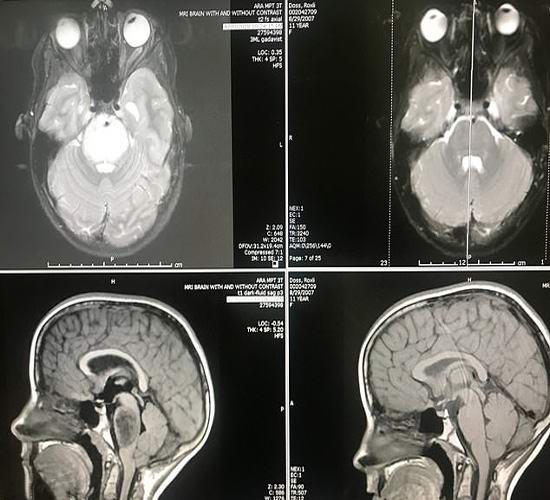

A na presenečenje vseh se napovedi zdravnikov niso uresničile. Več poleg tega je trenutno slikanje z magnetno resonanco kaže, da je tumor popolnoma izginil iz Roxleyjevih možganov! Zdravniki ne lahko najdejo racionalno razlago za to, kar se je zgodilo, ker po znanstvenih dokazih to preprosto ni mogoče. Zdravniki prepoznajo ki se še nikoli prej niso srečali tako spontano in hitra regresija velikega malignega možganskega tumorja. Potem zgodi se pravi čudež.

Redko agresiven tumor, ki ga letno najdejo v Dossu pojavlja se pri 200-300 Američanov in vsak od teh bolnikov velja za obsojene. Redko kdo od njih živi vsaj devet mesecev po odkritju bolezni. Tako je naša junakinja, sodeč je edinstven pacient. Zdravniki nameravajo previdno preuči dekličin imunski sistem, da ugotovi, kako kljub temu se je telo šolarke uspelo upreti smrtonosnemu bolezen.